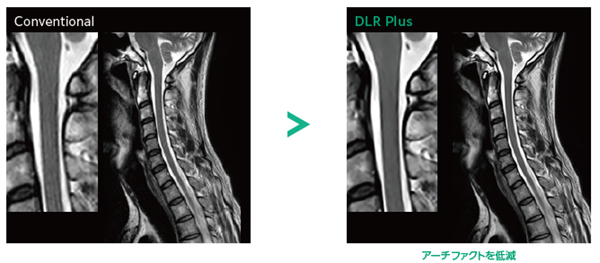

Deep Learning Reconstruction

SNRや鮮鋭度をあとからコントロール

Deep Learning技術を活用し※5,撮像終了後の画質調整を可能に。SNRを最適化するほか,MRI信号の処理を段階的に行うことで(k空間上の信号処理の工夫)画像の鮮鋭度を向上させます。これにより超解像度化やトランケーションアーチファクトを低減します。